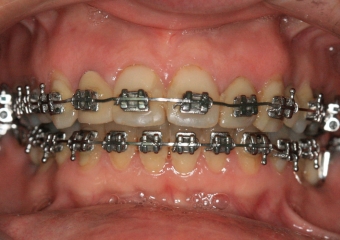

Mordida final